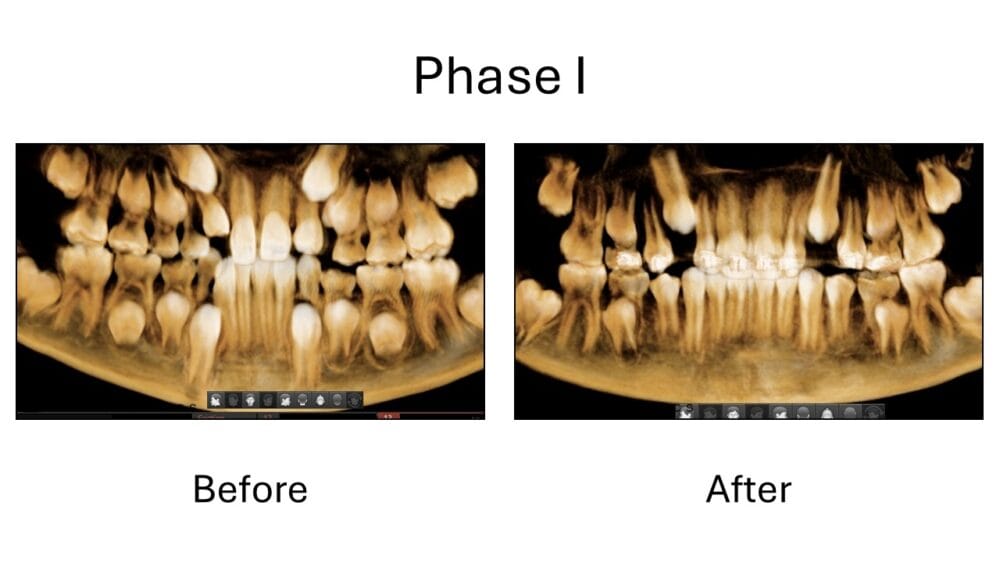

Look at these amazing smile transformations! Before and after orthodontic treatment photos. Braces before and after, clear aligner before and after, phase I before and after, and more. Click photos to enlarge.Â

At Boss Orthodontics, we take immense pride in our patientâs care and work diligently to achieve stunning orthodontic before and after transformations, showcasing the profound impact that orthodontic treatment has on our patients' smiles. Our before and after smile gallery highlights the remarkable changes achieved through braces and clear aligners/ Invisalign before and after treatment. Â Each transformation underscores our commitment to delivering personalized care and exceptional results, reflecting our dedication to enhancing both aesthetics and oral health.